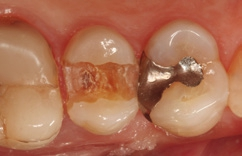

Bei der 55-jährigen Patientin imponierte eine okklusal penetrierte Sekundärkaries an dem Goldinlay an Zahn 15 (Abb. 8). Nach Aussage der Patientin war der Zahn seit ein paar Wochen aufbissempfindlich; die Vitalität war gegenüber Zahn 14 und 16 reduziert. Hieraus ergab sich die Behandlungsindikation zur Entfernung des Inlays und zur Vorbereitung einer endodontologischen Therapie. Nach der Entfernung des Inlays imponierte ein massiver Kariesbefall im gesamten Kavitätenbodenbereich (Abb. 9). Nach der Exkavation zeigten sich eine Verbindung zur Pulpa als auch diverse Infraktionslinien (Abb. 10). Die Verbindung zur Pulpa wurde interimsmäßig überkappt (TheraCal LC, Abb. 11); die Trepanation des Zahnes wurde dem Endodontologen überlassen. Vor einer endodontologischen Behandlung ist eine dichte adhäsive präendodontologische Aufbaufüllung essenziell. SDR flow+ hat die Indikation zur Aufbaufüllung in seinem Indikationsspektrum.